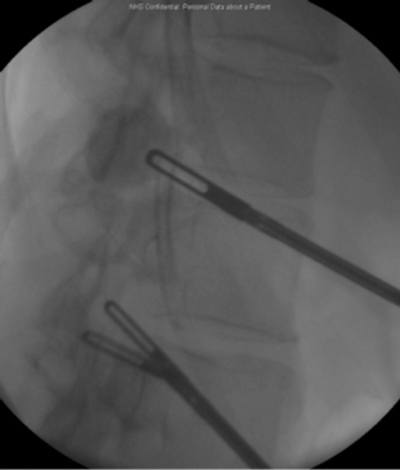

Percutaneous nephrolithotomy (PCNL) failed. Although the calyx was successfully punctured, due to the lack of overlying cortex, no track could be established.

Marking for PCNL access.